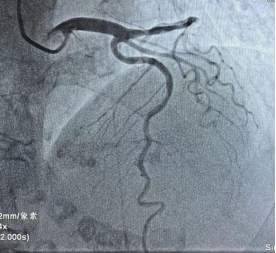

右冠脉细小,未见明显狭窄